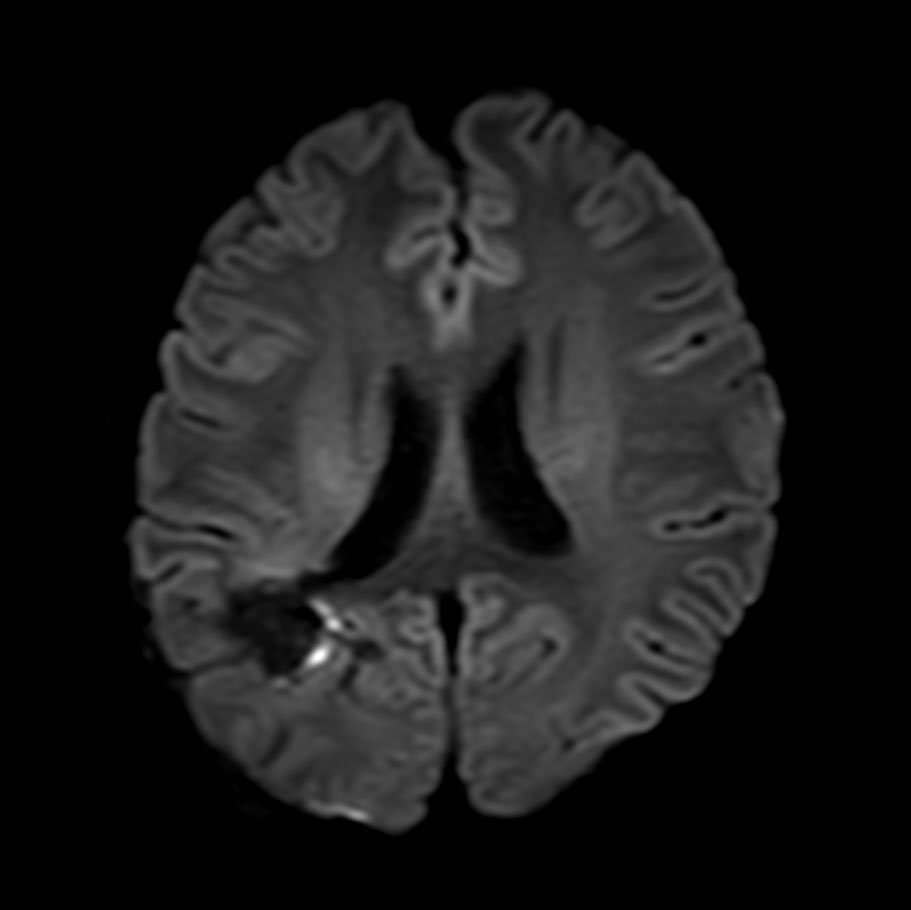

Axial DWI (b1200)